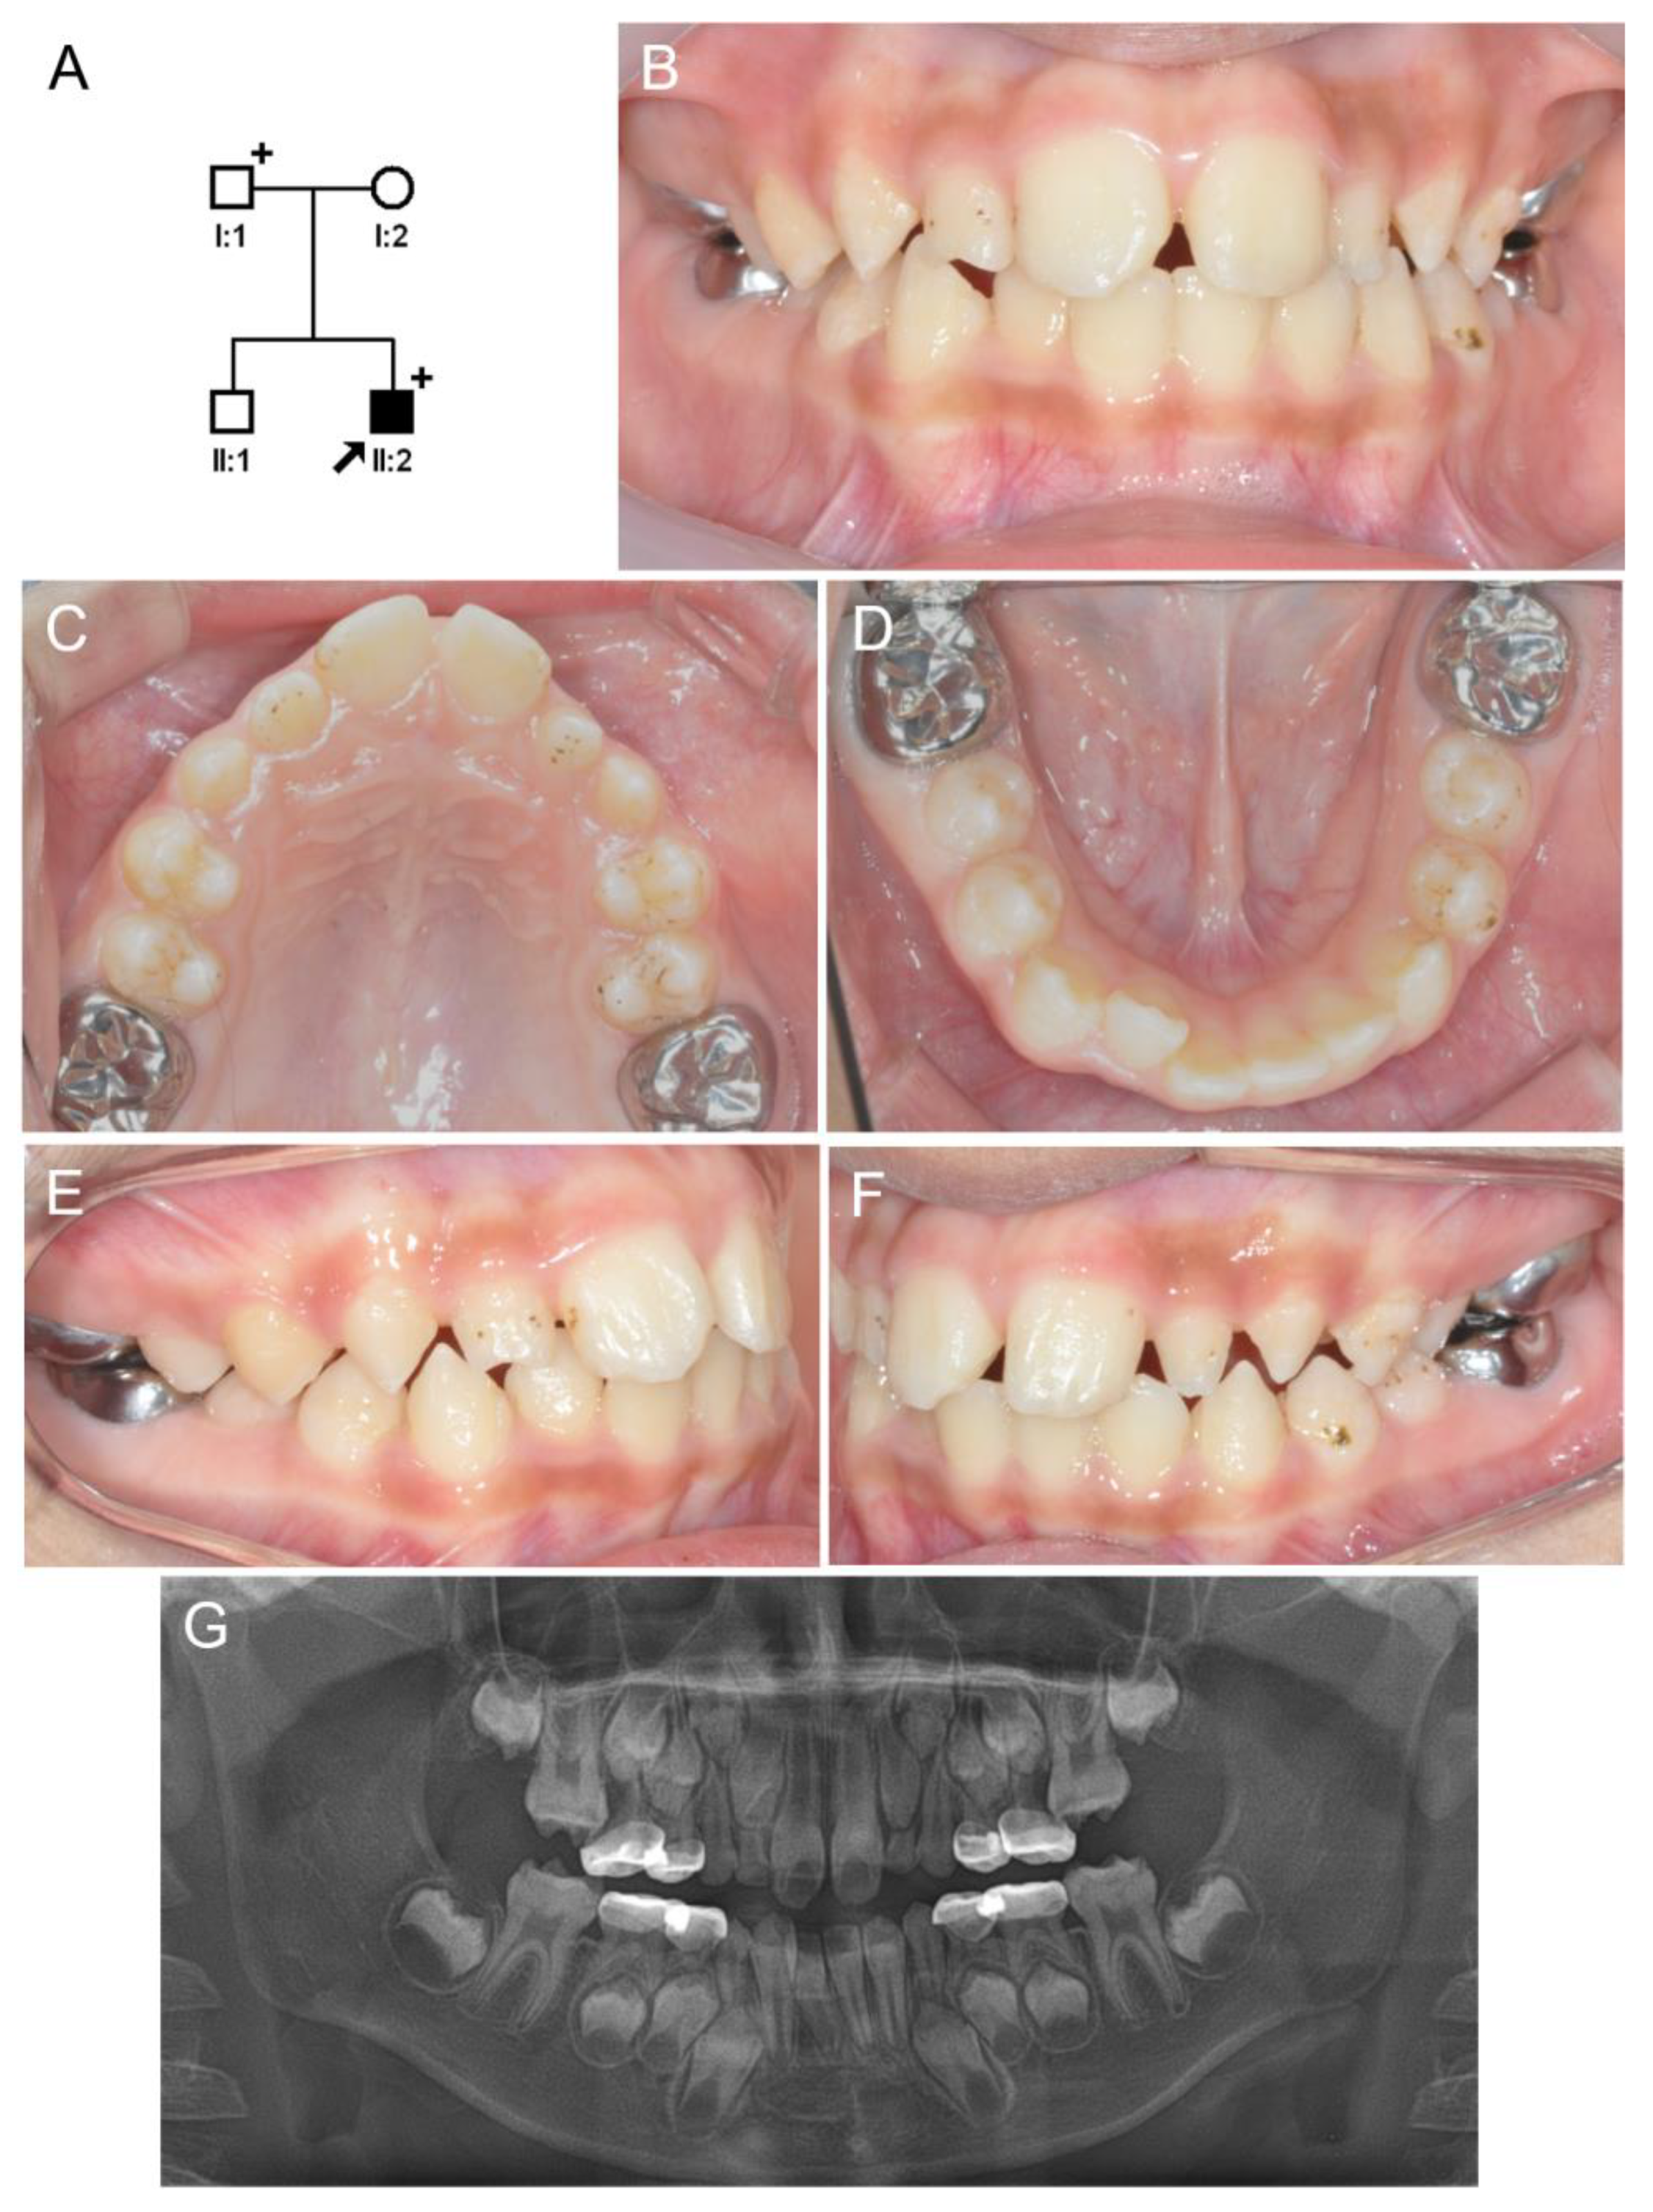

3.2. Family 2